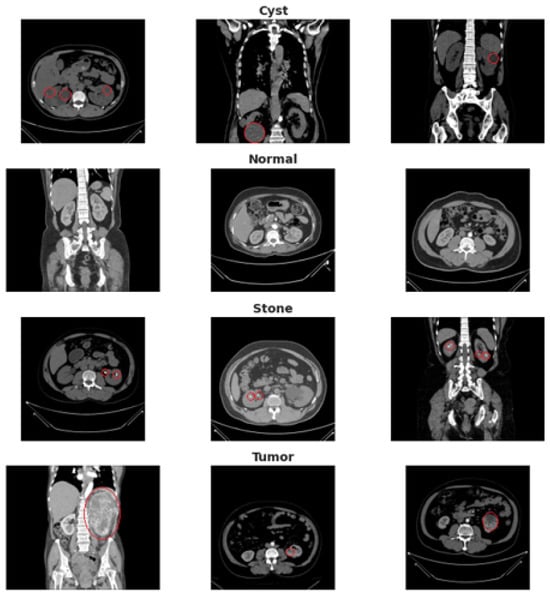

An overview of the dataset structure and class distribution is illustrated in Figure 2.

Figure 2.

Dataset overview showing representative CT slices with corresponding annotations for Normal tissue, Cyst, Tumor, and Stone. The red circles highlight the region of interest (ROI) manually verified by the radiologist, indicating the precise anatomical location of the pathology in each example.